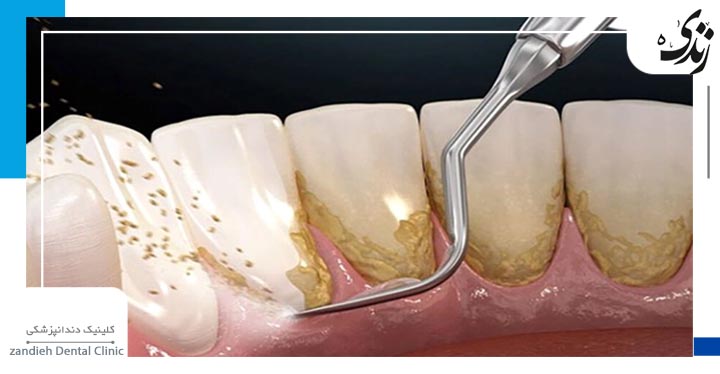

به فرآیند پاک سازی دندانها از رسوبات معدنی، پلاکهای میکروبی و جرم دندانی مجموعا جرم گیری دندان گفته می شود، که معمولاً توسط دندانپزشک انجام میشود. جرم گیری به صورت دستی یا با استفاده از دستگاههای اولتراسونیک انجام می شود. جرمگیری، مزایای متعددی دارد که درادامه به آن ها می پردازیم.

- جرم گیری توسط دندانپزشک یا بهداشت کار دندان با استفاده از ابزارهای دستی یا دستگاههای اولتراسونیک انجام میشود.